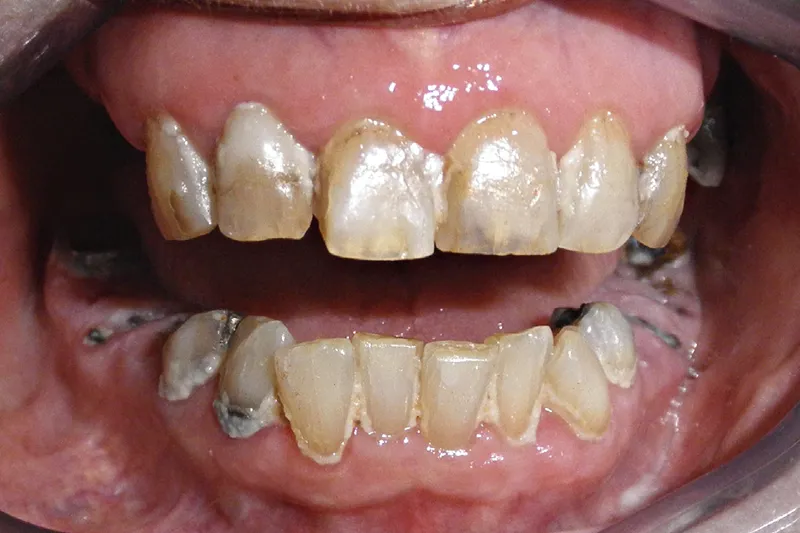

Baggrund – Mange skrøbelige ældre har dårlige tandsæt; stærkt destruerede tænder, som ikke kan restaureres, og rodrester med åbne rodkanaler ses hyppigt i kombination med periapikal og parodontal inflammation. Der ligger en stor udfordring for tandplejen i at forbedre den orale status for den voksende gruppe af skrøbelige ældre med egne tænder. Tandlæger er ofte usikre på, hvordan de skal håndtere rodrester og destruerede tænder uden mulighed for restaurering på skrøbelige ældre patienter.

Der bliver til stadighed en øget andel af ældre i befolkningen, og flere og flere beholder deres egne tænder hele livet. For en del borgere præges de sidste leveår af tiltagende fysisk og kognitiv svækkelse, hvilket kan medføre, at tandsættet forringes betydeligt. Tandlæger, der arbejder med ældre patienter, vil derfor ofte skulle tage stilling til, om rodrester og stærkt destruerede tænder skal ekstraheres, eller om patienten er bedre tjent med, at man lader dem sidde. Denne artikel angiver retningslinjer for, hvilke overvejelser man bør gøre sig, inden man beslutter sig for at ekstrahere – eller lade være.